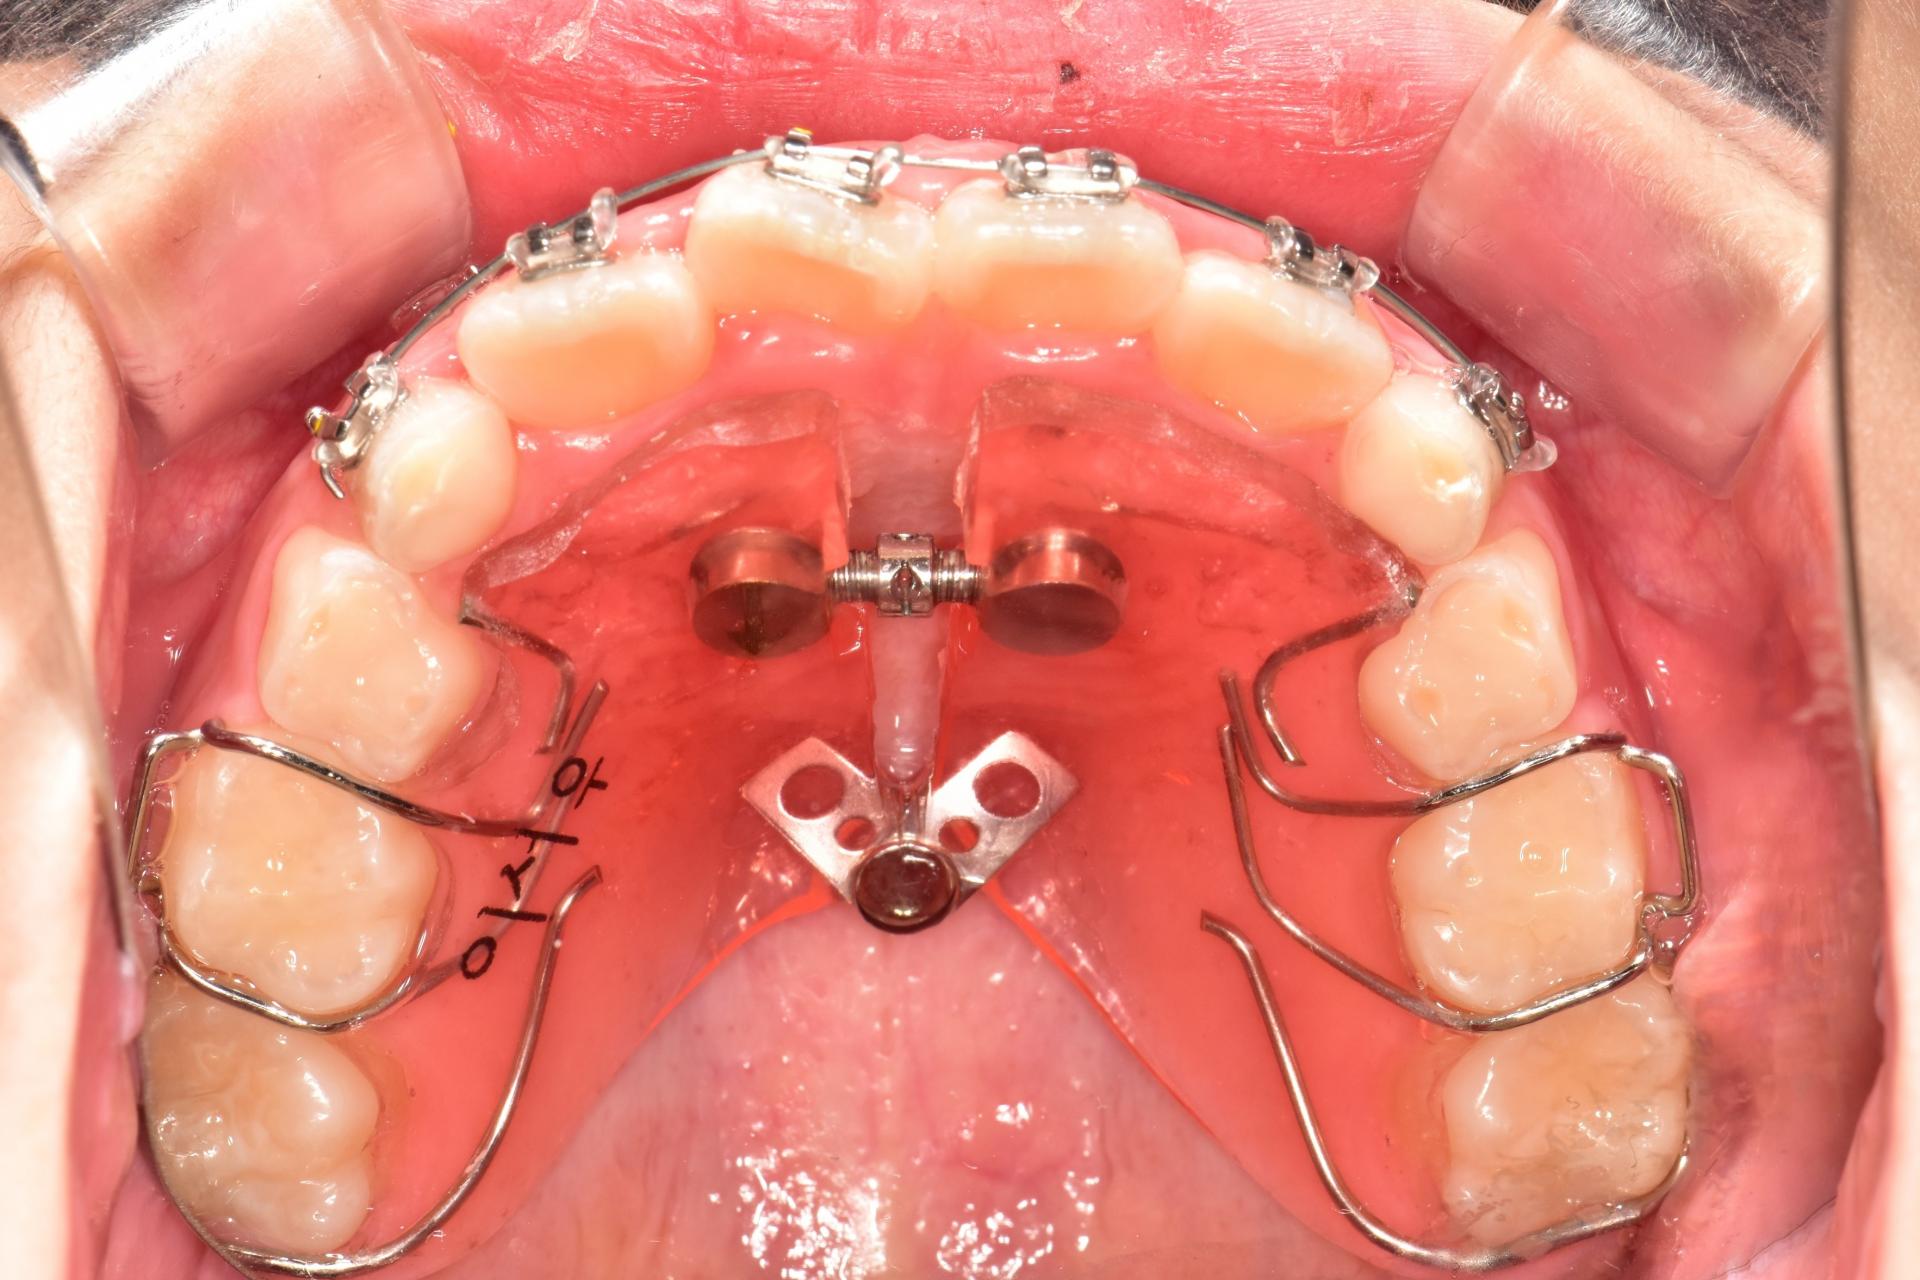

투명교정장치 착용중. 장치를 착용하여도 티가 나지 않습니다. 아이는 정말 성실하게 장치를 잘 껴주었습니다.